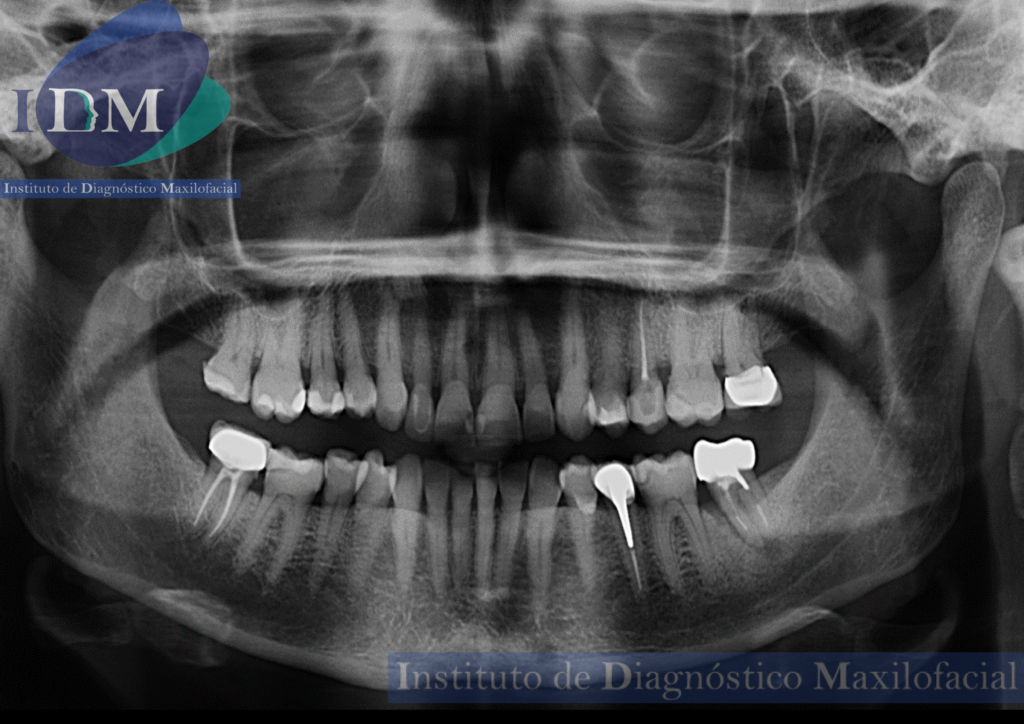

Radiografia Panorámica

A la evaluación de la radiografía panorámica se evidencia una neumatización alveolar de senos maxilares, reabsorción ósea alveolar bimaxilar con múltiples piezas con tratamientos restauradores y de obturación de conductos. Siendo lo mas resaltante un proceso osteolítico perirradicular de la pieza 3.7.